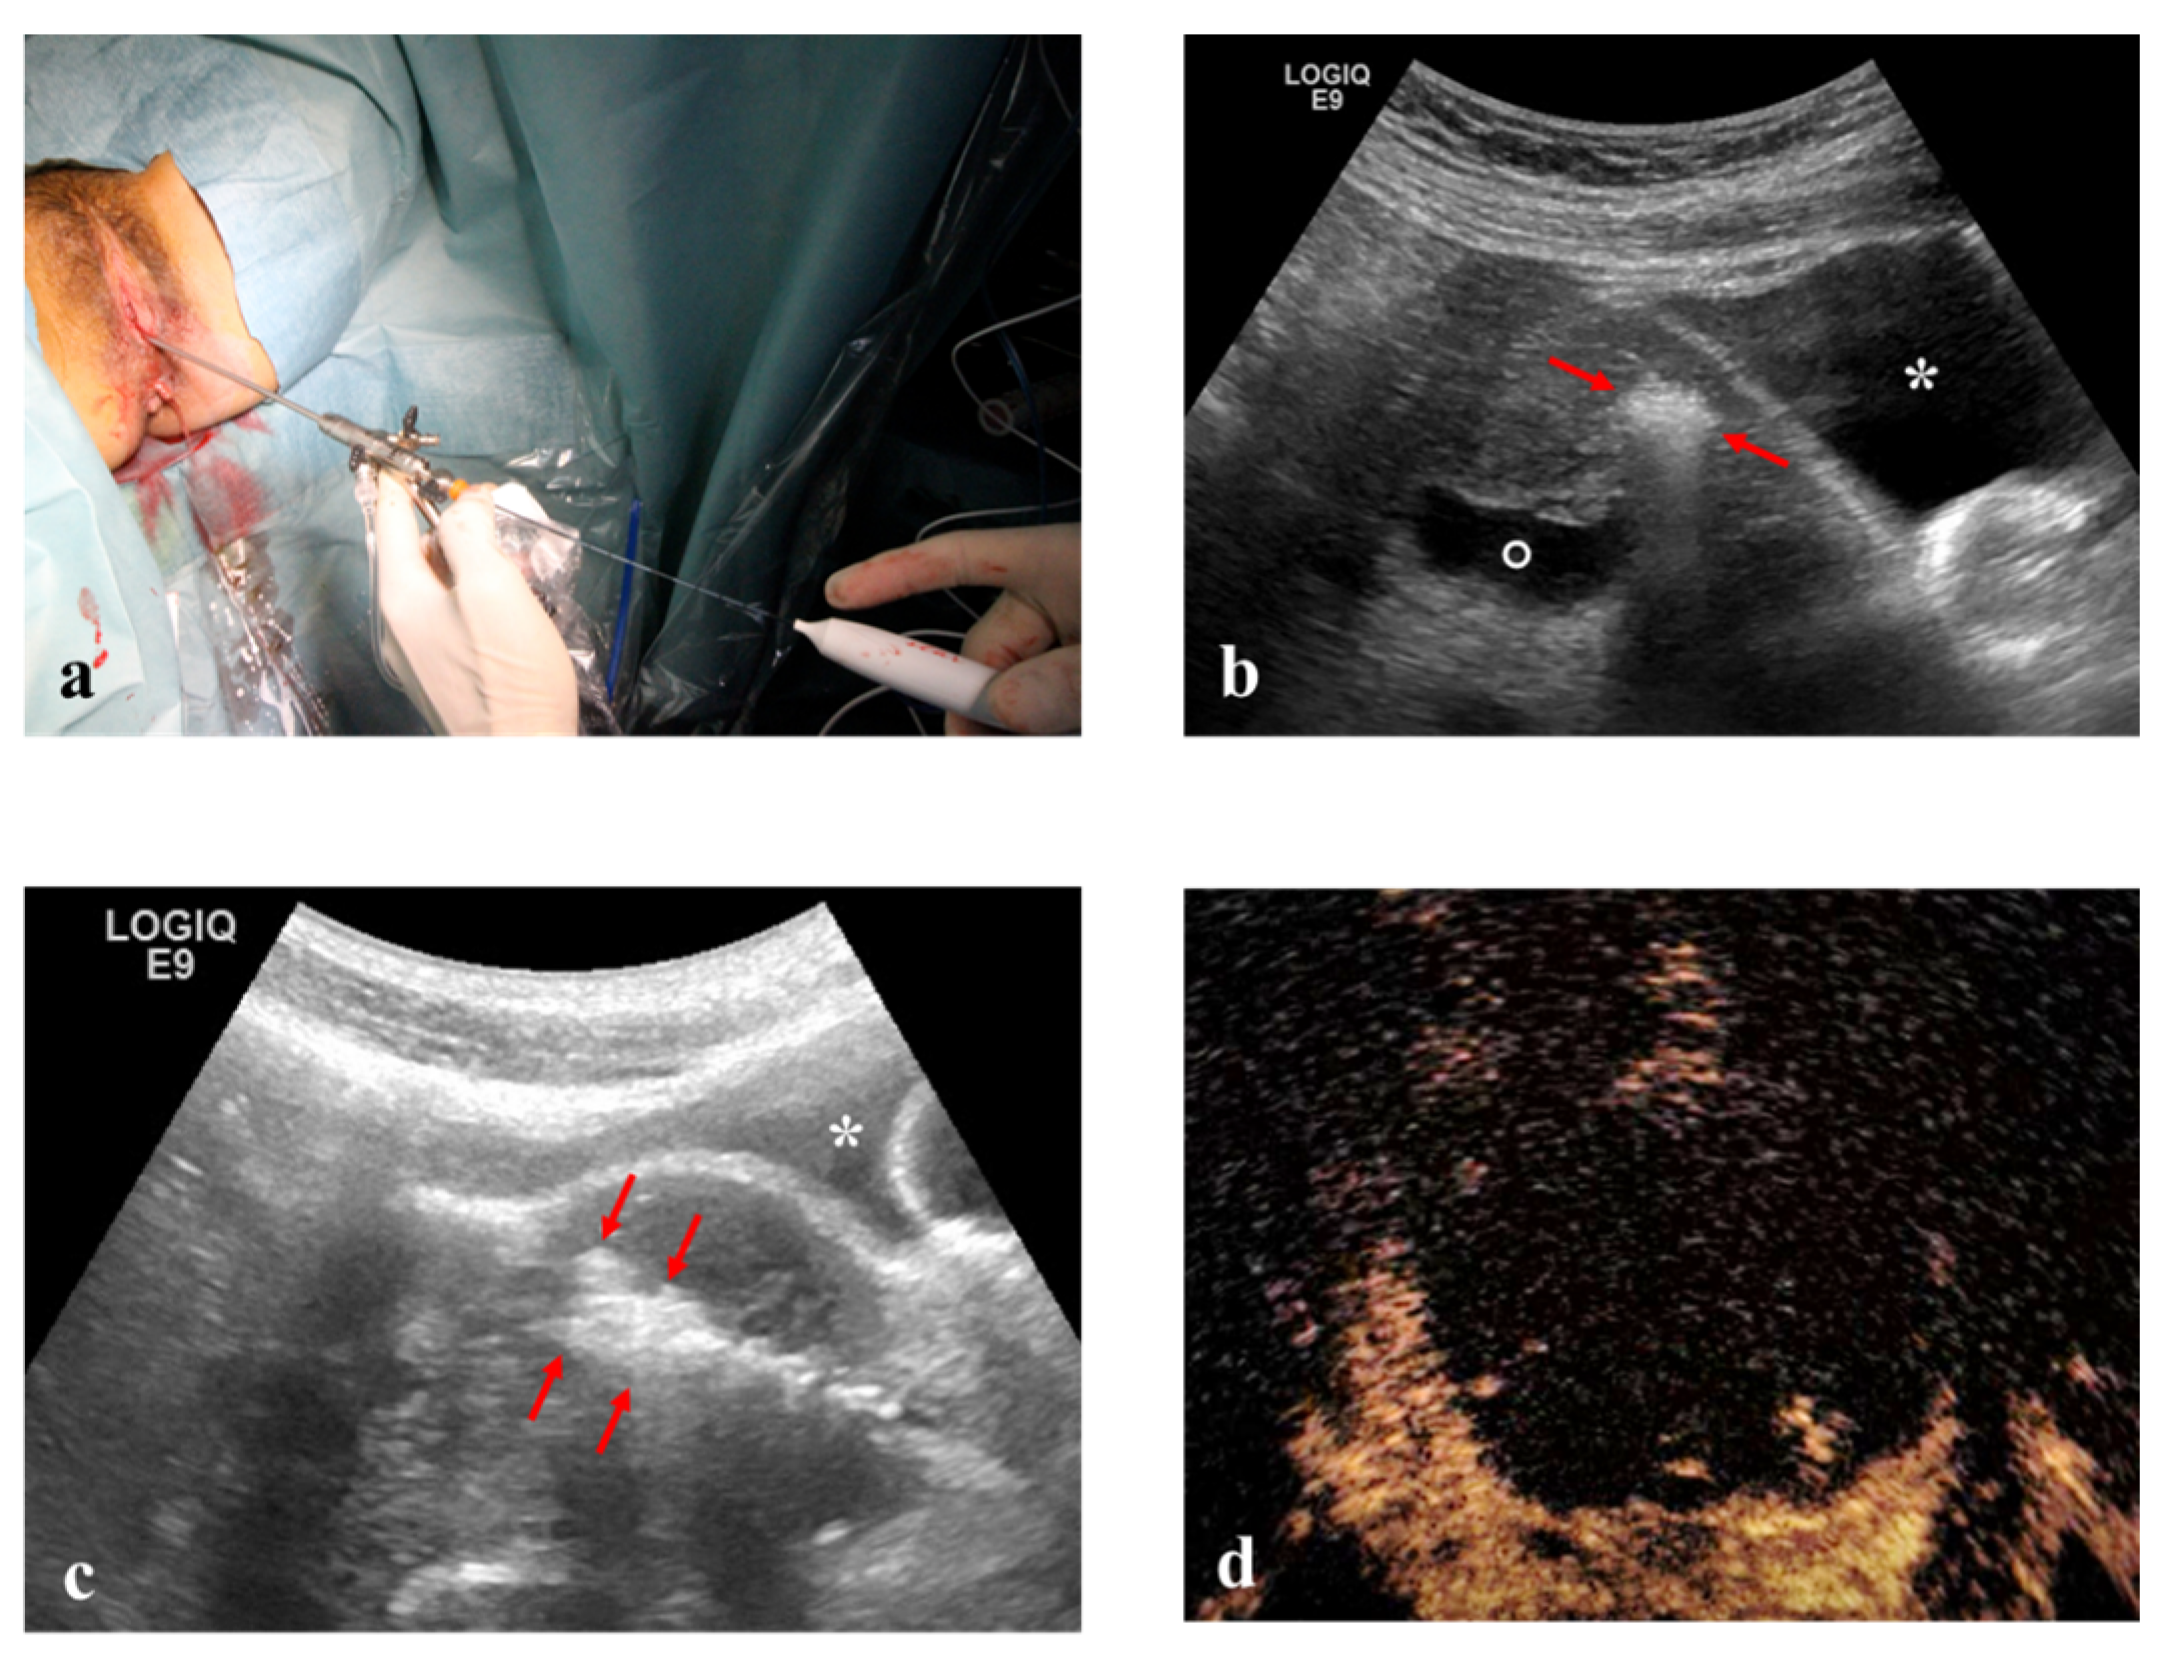

Hysteroscopic RFM: unconscious sedation or spinal anesthesia and dorsal position were performed on an outpatient basis. Standard hysteroscopic instrumentation (Outer diameter 3.8 mm and straight 5 French (Fr) working channel, Wolf Medical Instruments, Germany) (Figure 4), and trans-abdominal ultrasonography for intra-uterine needle guidance.

Figure 4. (a) RF electrode inserted into 5 Fr. working channel of a 3.8 mm hysteroscope. (b) and (c) Intra-operative TA ultrasound shows hyper-echogenicity of RF ablation of an anterior myoma (arrowheads) between the bladder (asterisk) and the endometrial cavity (empty point). (d) Echo-enhanced area after complete RF ablation of the fibroid.